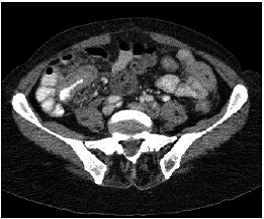

At the moment of hospitalization, the patient did not present any sign of rheumatoid arthritis activity (Clinical Diseases Activity Index: 0). A computed tomography (CT) scan of the brain was done showing a hypodense basal right lesion associated with vasogenic edema in the left frontal lobe upon which extension studies were requested. Brain magnetic resonance imaging showed supraand infratentorial lesions highly suggestive of caseous granulomas (figure 1). A chest CT showed centrilobular micronodules with soft tissue density and branched centrilobular linear densities (figure 2). Abdomino-pelvic CT showed iliac mesenteric and retroperitoneal lymphadenopathy and wall thickening of the distal ileum (figure 3), which is highly suggestive of tuberculosis as a first diagnostic possibility. Lymph node biopsy reported granulomatous lymphadenitis with acid-alcohol resistant bacilli, thus confirming the diagnosis.